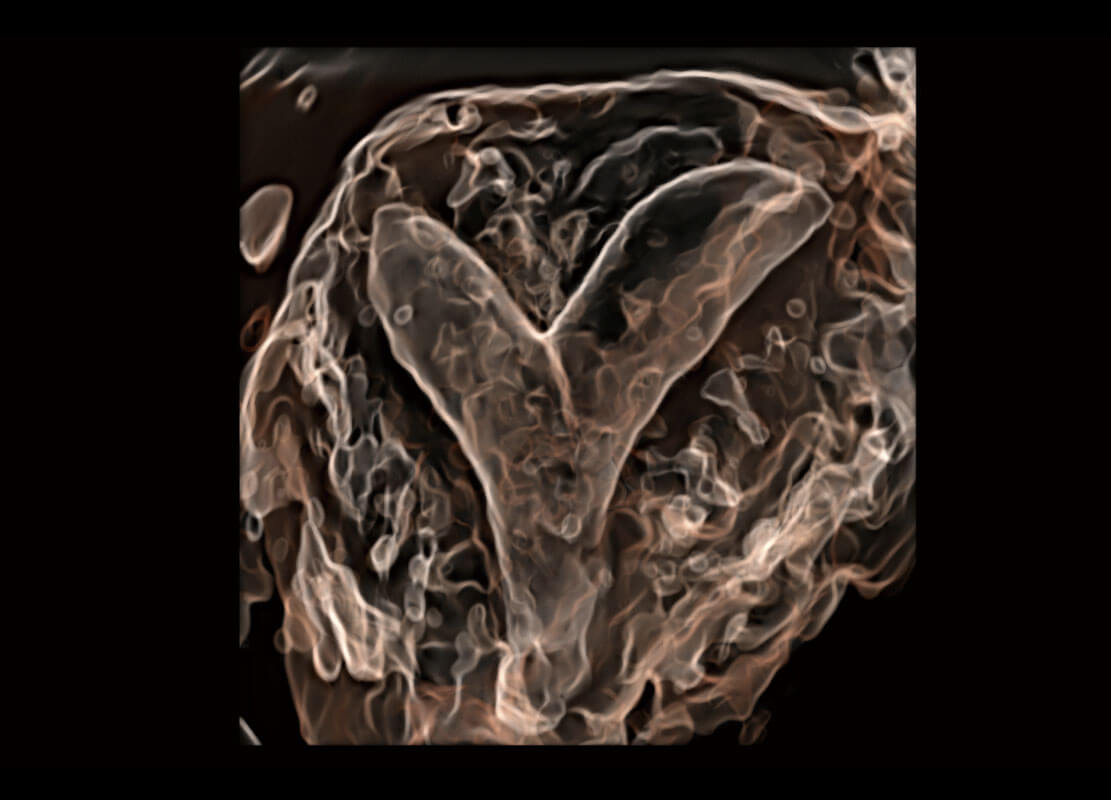

• 右室双出口

• 胎心容积成像